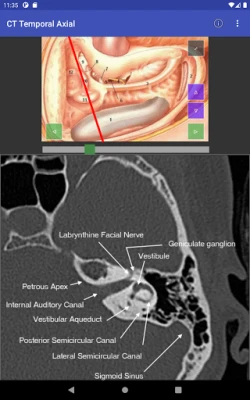

Domin sauƙaƙa fahimtar tsarin jikin ɗan adam ta hanyar hotunan CT scan, mun haɗa abubuwan ciki a matakai biyu (planes). Ɗaya daga ciki yana aiki a matsayin jagora (reference) wanda zai taimaka wajen fahimtar ɗayan sosai. Wannan hanya tana sa fahimtar tsarin jikin ya zama mai sauƙi da inganci, kamar yadda ake fuskanta a yanayin asibiti na gaskiya. Bugu da ƙari, za a iya gungurawa (scrolled) kowane mataki daban-daban, wanda hakan ke ba da damar fahimtar zurfin kowane sashi da cikakkun bayanansa cikin sauƙi.